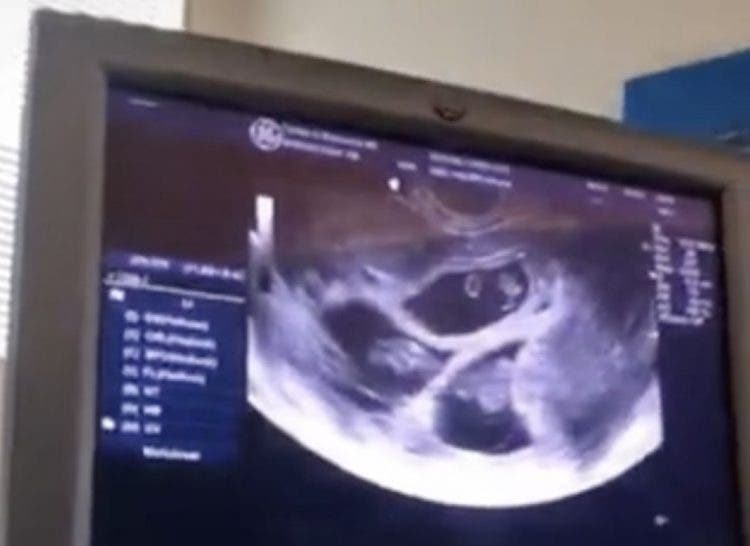

Es un extraño caso de Superfetación que dio como resultado un tercer bebé que sería unos días “menor” que los gemelos. La futura madre no sabía que algo así podía ocurrir y quedó en shock. “Sabíamos que eran dos embarazos separados. Nuestros primeros bebés tienen 11 días más que nuestro tercer bebé”, dijo la chica.

Los médicos quieren asegurarse de que todo vaya bien así que están realizando pruebas cada dos semanas para monitorear el crecimiento de los bebés. Se encuentran atentos a otros indicios que señalen que se trata de un caso de absorción gemelar.

“Somos afortunados de que los bebés tengan fechas cercanas para que puedan nacer el mismo día. Hay casos en los que los fetos se llevan meses de diferencia”, dijo la mujer. Quieren asegurarse de que todos los bebés tengan el peso ideal y que se estén desarrollando sin problema.

“Sucedió porque mis hormonas no me impidieron ovular y volví a hacerlo en otro momento. No estaba tomando medicamentos para la fertilidad”, afirmó la futura madre.